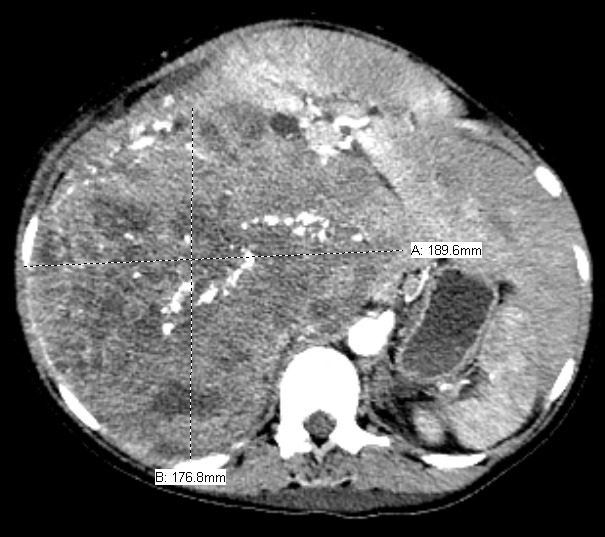

The patient delivered by spontaneous vaginal delivery at 37 weeks gestation. Her tachycardia persisted postpartum with heart rates exceeding 140 beats per minute, still of unexplained etiology. She developed a leukocytosis within the normal postpartum range but remained afebrile and without fundal tenderness. Due to increasing suspicion for malignancy, a computed tomography (CT) scan of the abdomen and pelvis was obtained, which showed a 19.0 x 17.7 x 22.5 cm heterogeneously enhancing soft tissue retroperitoneal mass with internal calcifications (Figures 1 and 2) and heterogeneously enhancing masses of various sizes in the liver and abdominal wall concerning for metastatic GIST (Figure 3). On postpartum day six, CT angiography of the chest was performed due to persistent tachycardia in the setting of a new diagnosis of a malignancy, which showed a right anterior lower lobe segmental and subsegmental pulmonary embolus. The patient was started on therapeutic low-molecular-weight heparin and trans-thoracic echocardiography was performed, which was unremarkable.